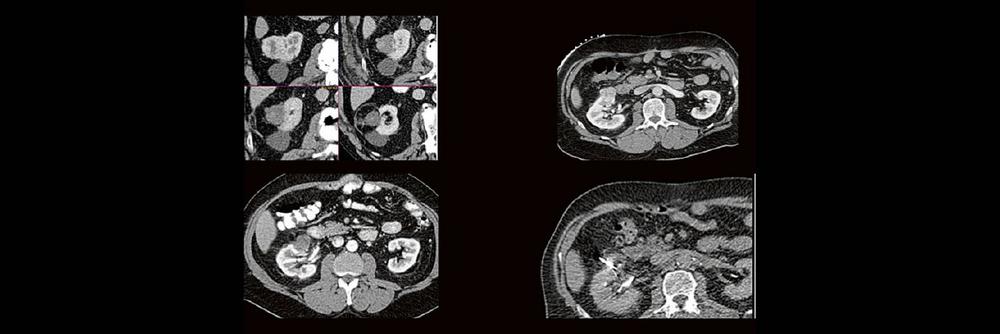

Dr. med. Sascha Alexander Pietruschka Die Anwendung von ablativen Verfahren hat sich in der klinischen Praxis etabliert. Nierentumoren bieten sich…